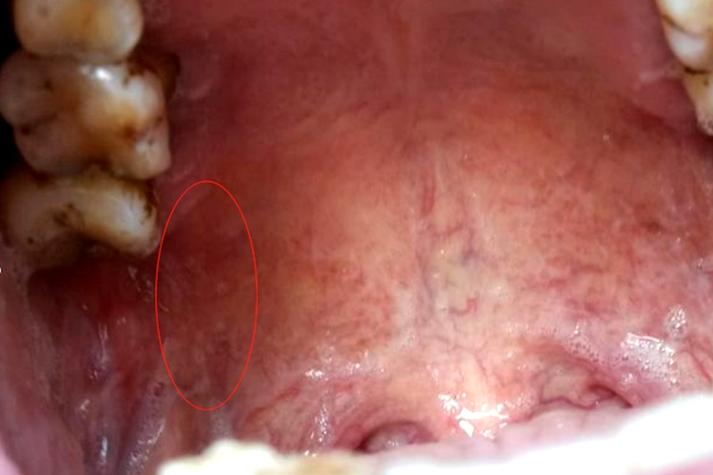

需要警惕的少数情况(建议就医)

虽然大部分情况是良性的,但如果出现以下“警报信号”,建议您及时去看医生(口腔黏膜科或口腔颌面外科):

(图片来源网络,侵删)

- 颗粒迅速增大或形态改变:短时间内小颗粒明显变大,或者形状变得不规则。

- 颜色异常:颗粒的颜色变为深红色、紫色、黑色或出现白斑、红斑相间。

- 伴有疼痛或溃疡:颗粒本身持续疼痛,或者表面破溃形成长期不愈合的溃疡(超过2周)。

- 质地变硬:触摸时感觉非常坚硬,像石头一样。

- 出现麻木或感觉异常:上颚或舌头出现麻木、刺痛等异常感觉。

- 伴有颈部淋巴结肿大:下巴或脖子下方的淋巴结肿大、疼痛。

- 反复出现:同一个位置的小颗粒反复破溃、愈合、再出现。